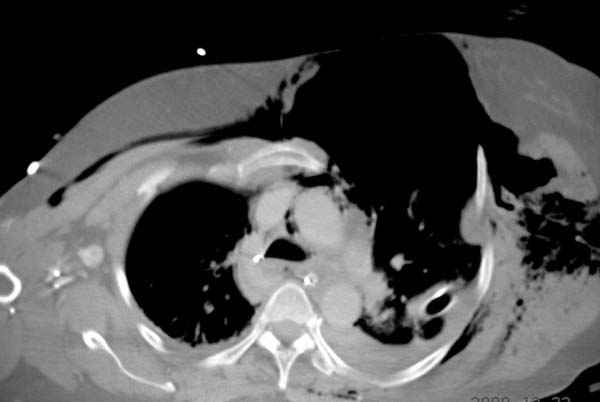

К нам поступила больная 56 лет после автоаварии в бессознательном состоянии, которая срочно заинтубирована в приемном отделении и сделаны необходимые исследования. Данные КТ и рентген показали перелом дистального бедра и Dissociation upper extremity - закрытый отрыв левой верхней конечности на уровне грудинно-ключичного сочленения и множественные переломы ребер.

На поверхности грудной клетки из-за полного разрыва грудной мышцы под кожей заметно биение сердца и след от ремня безопасности. Грудная клетка расширена из-за смещения верхней конечности вверх и латерально. Признаков васкулярного повреждения нет, и из-за отсутствия сознания не смогли определить наличия повреждения нервов.

Срочно в операционной наложен наружный фиксатор и травма хирургом поставлены трубки в плевральную полость.